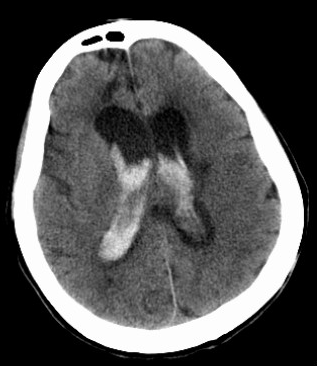

脑室出血

责任血管:脉络丛血管

病因:高血压、脉络丛动脉瘤、脑动静脉血管畸形、Moyamoya 病、脑室内肿瘤、血液病

症状体征: